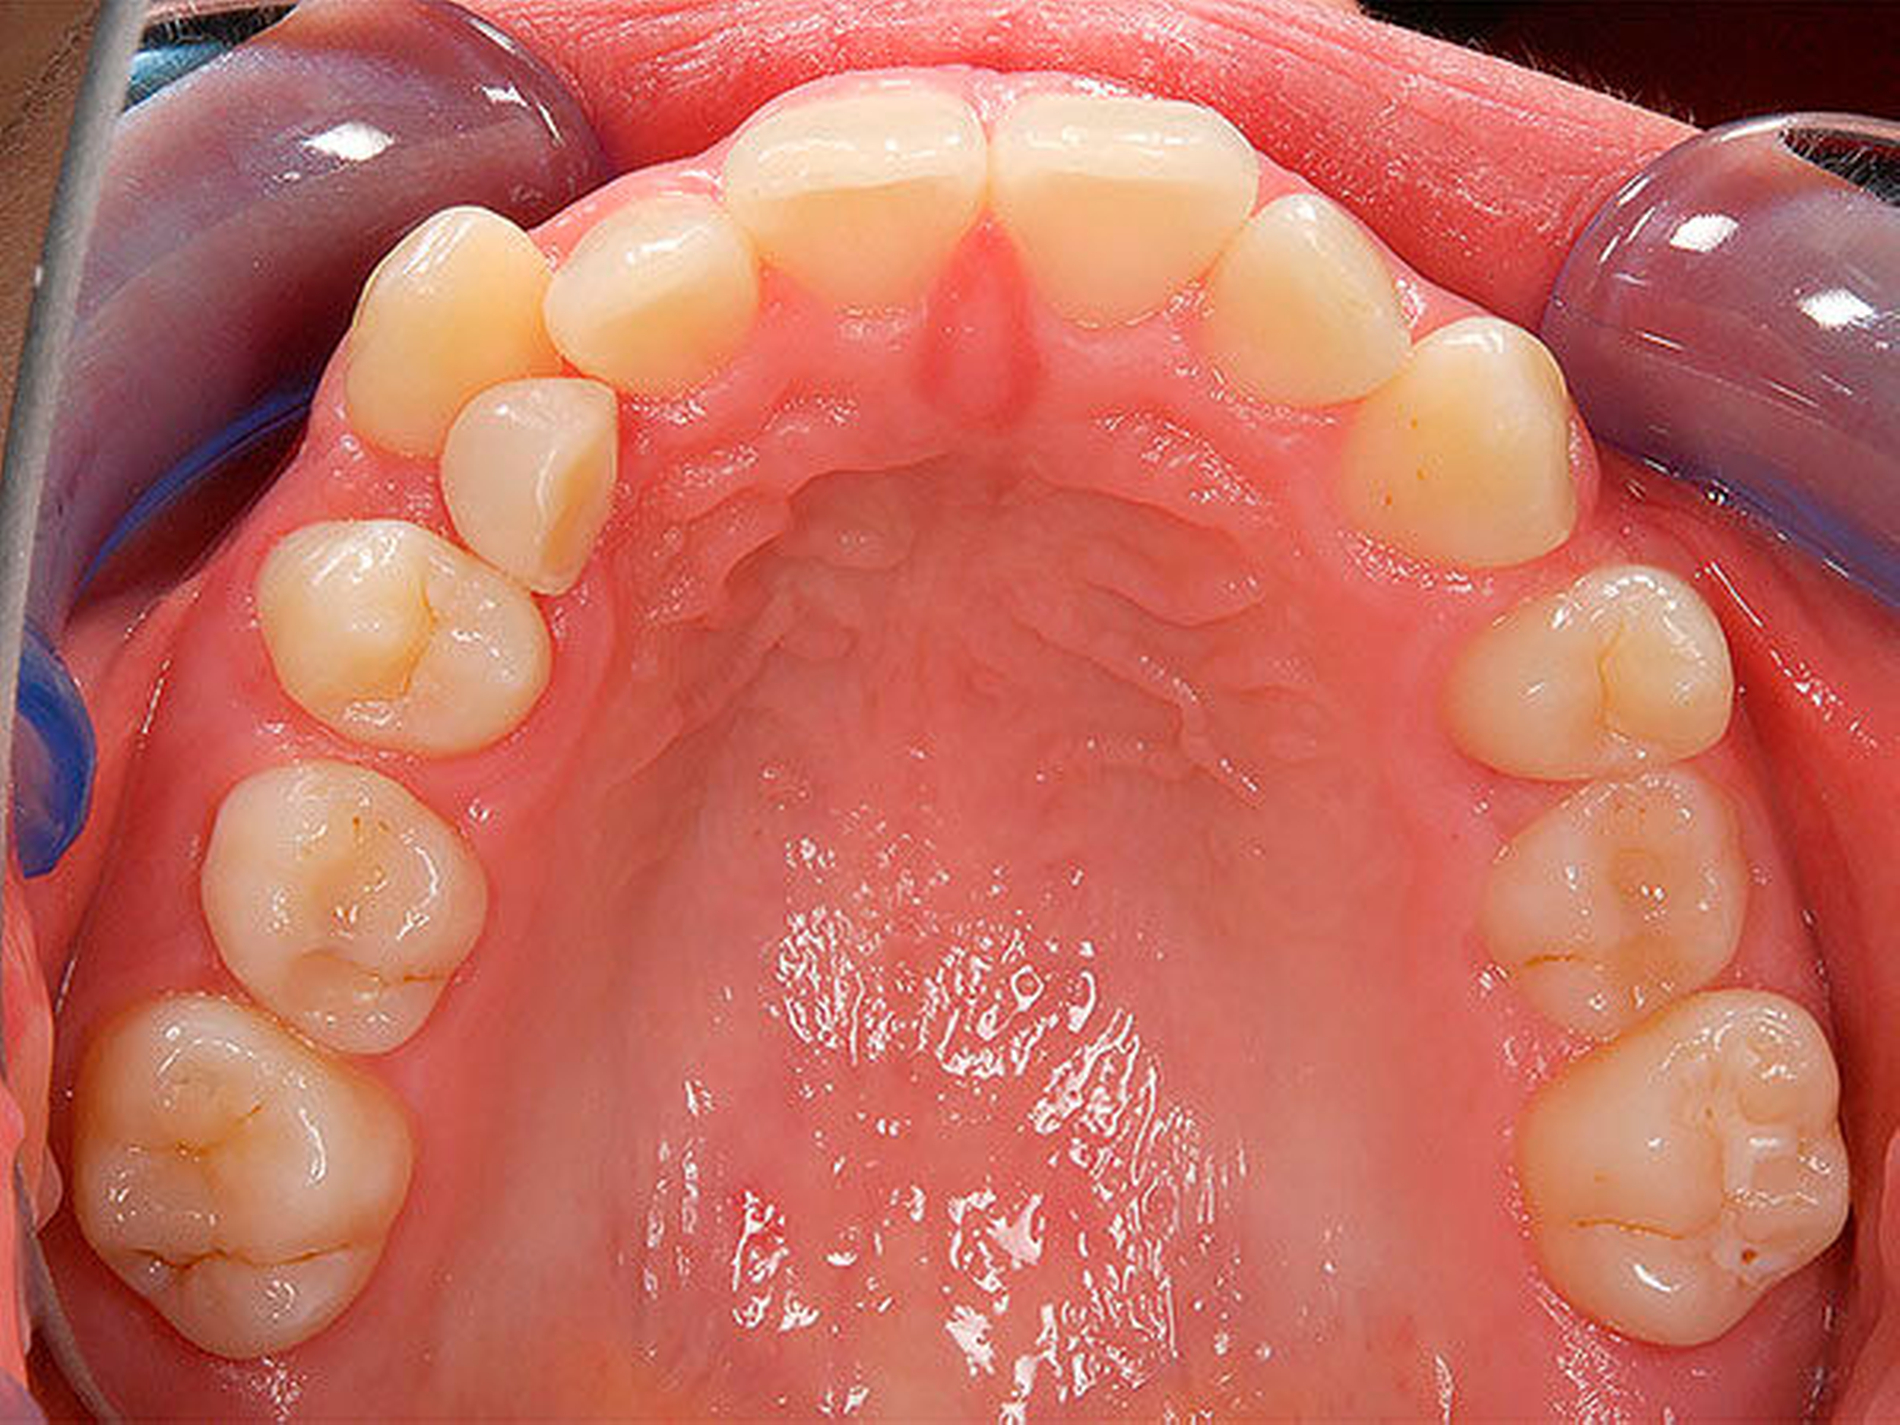

Besonders wichtig ist aus zahnärztlich-kieferorthopädischer Sicht die Beurteilung der lateralen Okklusionsverhältnisse [Kahl-Nieke, 2015]. Der unilaterale Kreuzbiss kommt ungefähr viermal häufiger vor als der bilaterale [Schopf, 2003]. Bei 80 Prozent der Kinder mit einseitigem Kreuzbiss tritt eine funktionelle Unterkieferabweichung auf [Kurol, 1992] und die Unterkiefermitte verschiebt sich dabei zur Kreuzbissseite [Santos Pinto, 2001] bei gleichzeitig asymmetrischer Kondylenposition. Diese reflektorische Einnahme der Kreuzbissstellung vergrößert die Anzahl der Okklusionskontakte, mit der Gefahr, dass nach kurzer Zeit diese transversale Fehlstellung des Unterkiefers neuromuskulär fixiert wird. Bei Belassen des Kreuzbisses kann eine skelettale Manifestation der Asymmetrie und eine dauerhafte Abweichung der Kinnmitte von der Gesichtsmitte resultieren [Hesse, 1997; O`byrn, 1995]. Erfolgt keine frühzeitige Therapie, besteht zudem die Gefahr einer Wachstumshemmung im Bereich der im Kreuzbiss „eingefangenen“ Oberkieferseite. Eine kieferorthopädische Frühbehandlung scheint präventiv gegen eine skelettale Adaptation und gegen eine Persistenz des Kreuzbisses in die permanente Dentition zu wirken [Harrison, 2001]. Das Überstellen des lateralen Kreuzbisses durch transversale Weitung des Oberkiefers kann beispielsweise mittels forcierter Gaumennahterweiterung [Köbel, 2017] erfolgen und wirkt sich neben einer Verbesserung der respiratorischen Situation günstig auf die Beseitigung skelettaler und dentoalveolärer Asymmetrien aus [Hesse, 1997; Santos Pinto, 2001] (Abbildung 3).